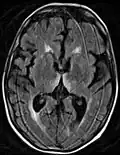

Axial MRI FLAIR image showing hyperintense signal in the mesial dorsal thalami, a common finding in Wernicke encephalopathy. This patient was nearly in coma when IV thiamine was started, he responded moderately well but was left with some Korsakoff type deficits. Axial MRI FLAIR image showing hyperintense signal in the mesial dorsal thalami, a common finding in Wernicke encephalopathy. This patient was nearly in coma when IV thiamine was started, he responded moderately well but was left with some Korsakoff type deficits.